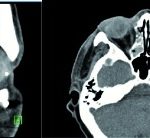

Gegebenenfalls findet sich im Dünnschicht- CT des Felsenbeins freie Luft in der Cochlea. Auf Grund des kurzen Zeitfensters von etwa 48 bis 72 Stunden sind eine umgehende Tympanoskopie und Abdeckung der Rundfenstermembran durch den HNO-Facharzt erforderlich. Die Protektion der Region um die Rundfenstermembran mit zum Beispiel Bindegewebe verhindert einen weiteren Austritt von Perilymphe und einen Eintritt von Keimen (5).

Im Audiogramm zeigte sich eine Schallleitungsstörung mit 30 dB pantonal und einer Schallempfindungsstörung von inzwischen 35 dB bei 1 – 6 kHz. Intraoperativ war neben einem Defekt des hinteren oberen Quadranten des Trommelfells eine für die Schallübertragung bedeutsame Hammerkopf- Fixation feststellbar (Abb 3). Auf Grund der Lokalisation des Defektes entschieden wir uns für eine endaurale Schnittführung und für eine Transplantatgewinnung im Bereich des Tragus- Knorpels (Abb 4). Es folgte die Anfrischung der Perforationsränder über einen endauralen Zugang (Abb 5). Danach wurde eine Prothese (Titan PORP, Typ Tübingen) zur Wiederherstellung der Schallübertragung über die restliche Gehörknöchelchenkette (Malleus und Stapes) eingesetzt (Abb 6 a-f).